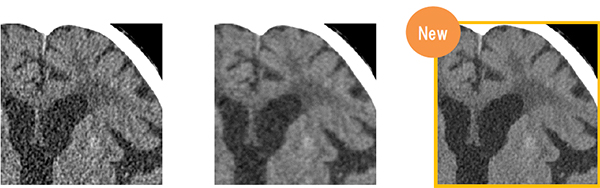

逐次近似画像処理“IPV”は,自然な質感を保ったまま,最大90%の画像ノイズ低減や,最大83%の被ばく低減などを可能にし,低被ばくと高画質を高いレベルで両立できる画像処理法である。今回,適応領域が従来の腹部だけでなく,頭部や胸部も含めた全身へと広がった。高画質化についてはさらに,金属アーチファクト低減技術“HiMAR”が進化し,“HiMAR Plus”が追加された。HiMAR Plusは,rawデータとイメージデータの両方で繰り返し再構成を行うことで,より強いアーチファクトを抑制することができる。画像処理の強度は,standardとstrongの2段階が用意されている。アーチファクトを除去しやすい腰椎などには高速に処理できる従来のHiMARを,大腿や膝など大きな金属が入っている部分にはHiMAR Plusを使用するなど,撮影画像を確認して必要に応じた処理が可能になる。

IPVによる画質改善(左からFPB,Intelli IP,IPV)(日立提供)